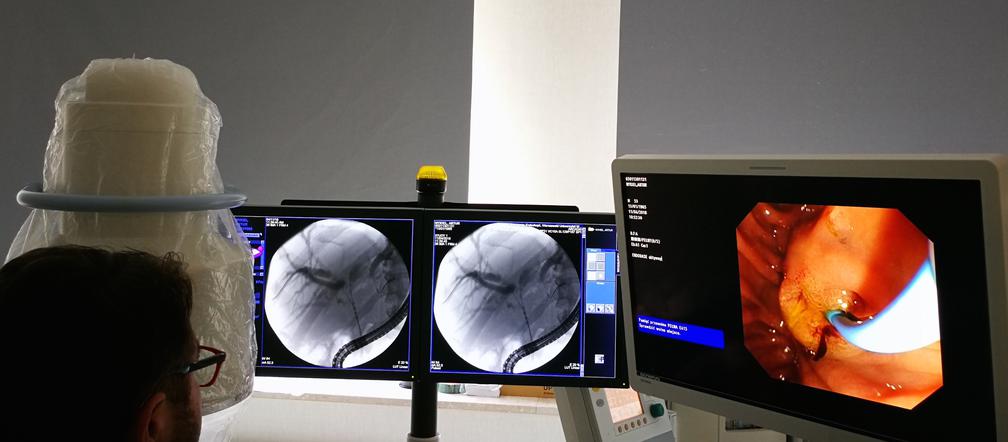

11 kwietnia br. Pracownia Endoskopowa Katedry i Kliniki Chirurgii Ogólnej, Transplantacyjnej i Wątroby WUM przeprowadziła dwa pierwsze w kraju zabiegi endoskopowej, endoluminalnej ablacji guzów wnęki wątroby falami radiowymi wysokiej częstotliwości (EL-RFA). Zabiegi wykonali dr Sławomir Kozieł i dr Jan Pertkiewicz wraz z zespołem pielęgniarskim i anestezjologicznym.

Zabiegi wykonano się w trakcie rutynowych endoskopowych cholangiografii wstecznych. Po usunięciu protez i zakontrastowaniu dróg żółciowych dokonano ich oceny radiologicznej, a następnie przez miejsce zwężenia przeprowadzono dwie prowadnice do prawego i lewego przewodu wątrobowego.

Następnie po prowadnikach, pod kontrolą fluoroskopii, wprowadzono do dróg żółciowych elektrodę średnicy 7Fr z końcówką roboczą długości 18mm. Po prawidłowym ustawieniu elektrody aplikowano  fale radiowe o mocy 7 W, przez 2 minuty, osiągając podgrzanie tkanki nowotworowej do temperatury 80 st.C.

Z uwagi na rozległość zmian pacjenci wymagali 3 aplikacji na każdą stronę dróg żółciowych (łączny czas aplikacji wyniósł po 12 minut). Po zakończeniu termoablacji ponownie skontrolowano radiologicznie drogi żółciowe wykluczając powstanie przetoki żółciowej.